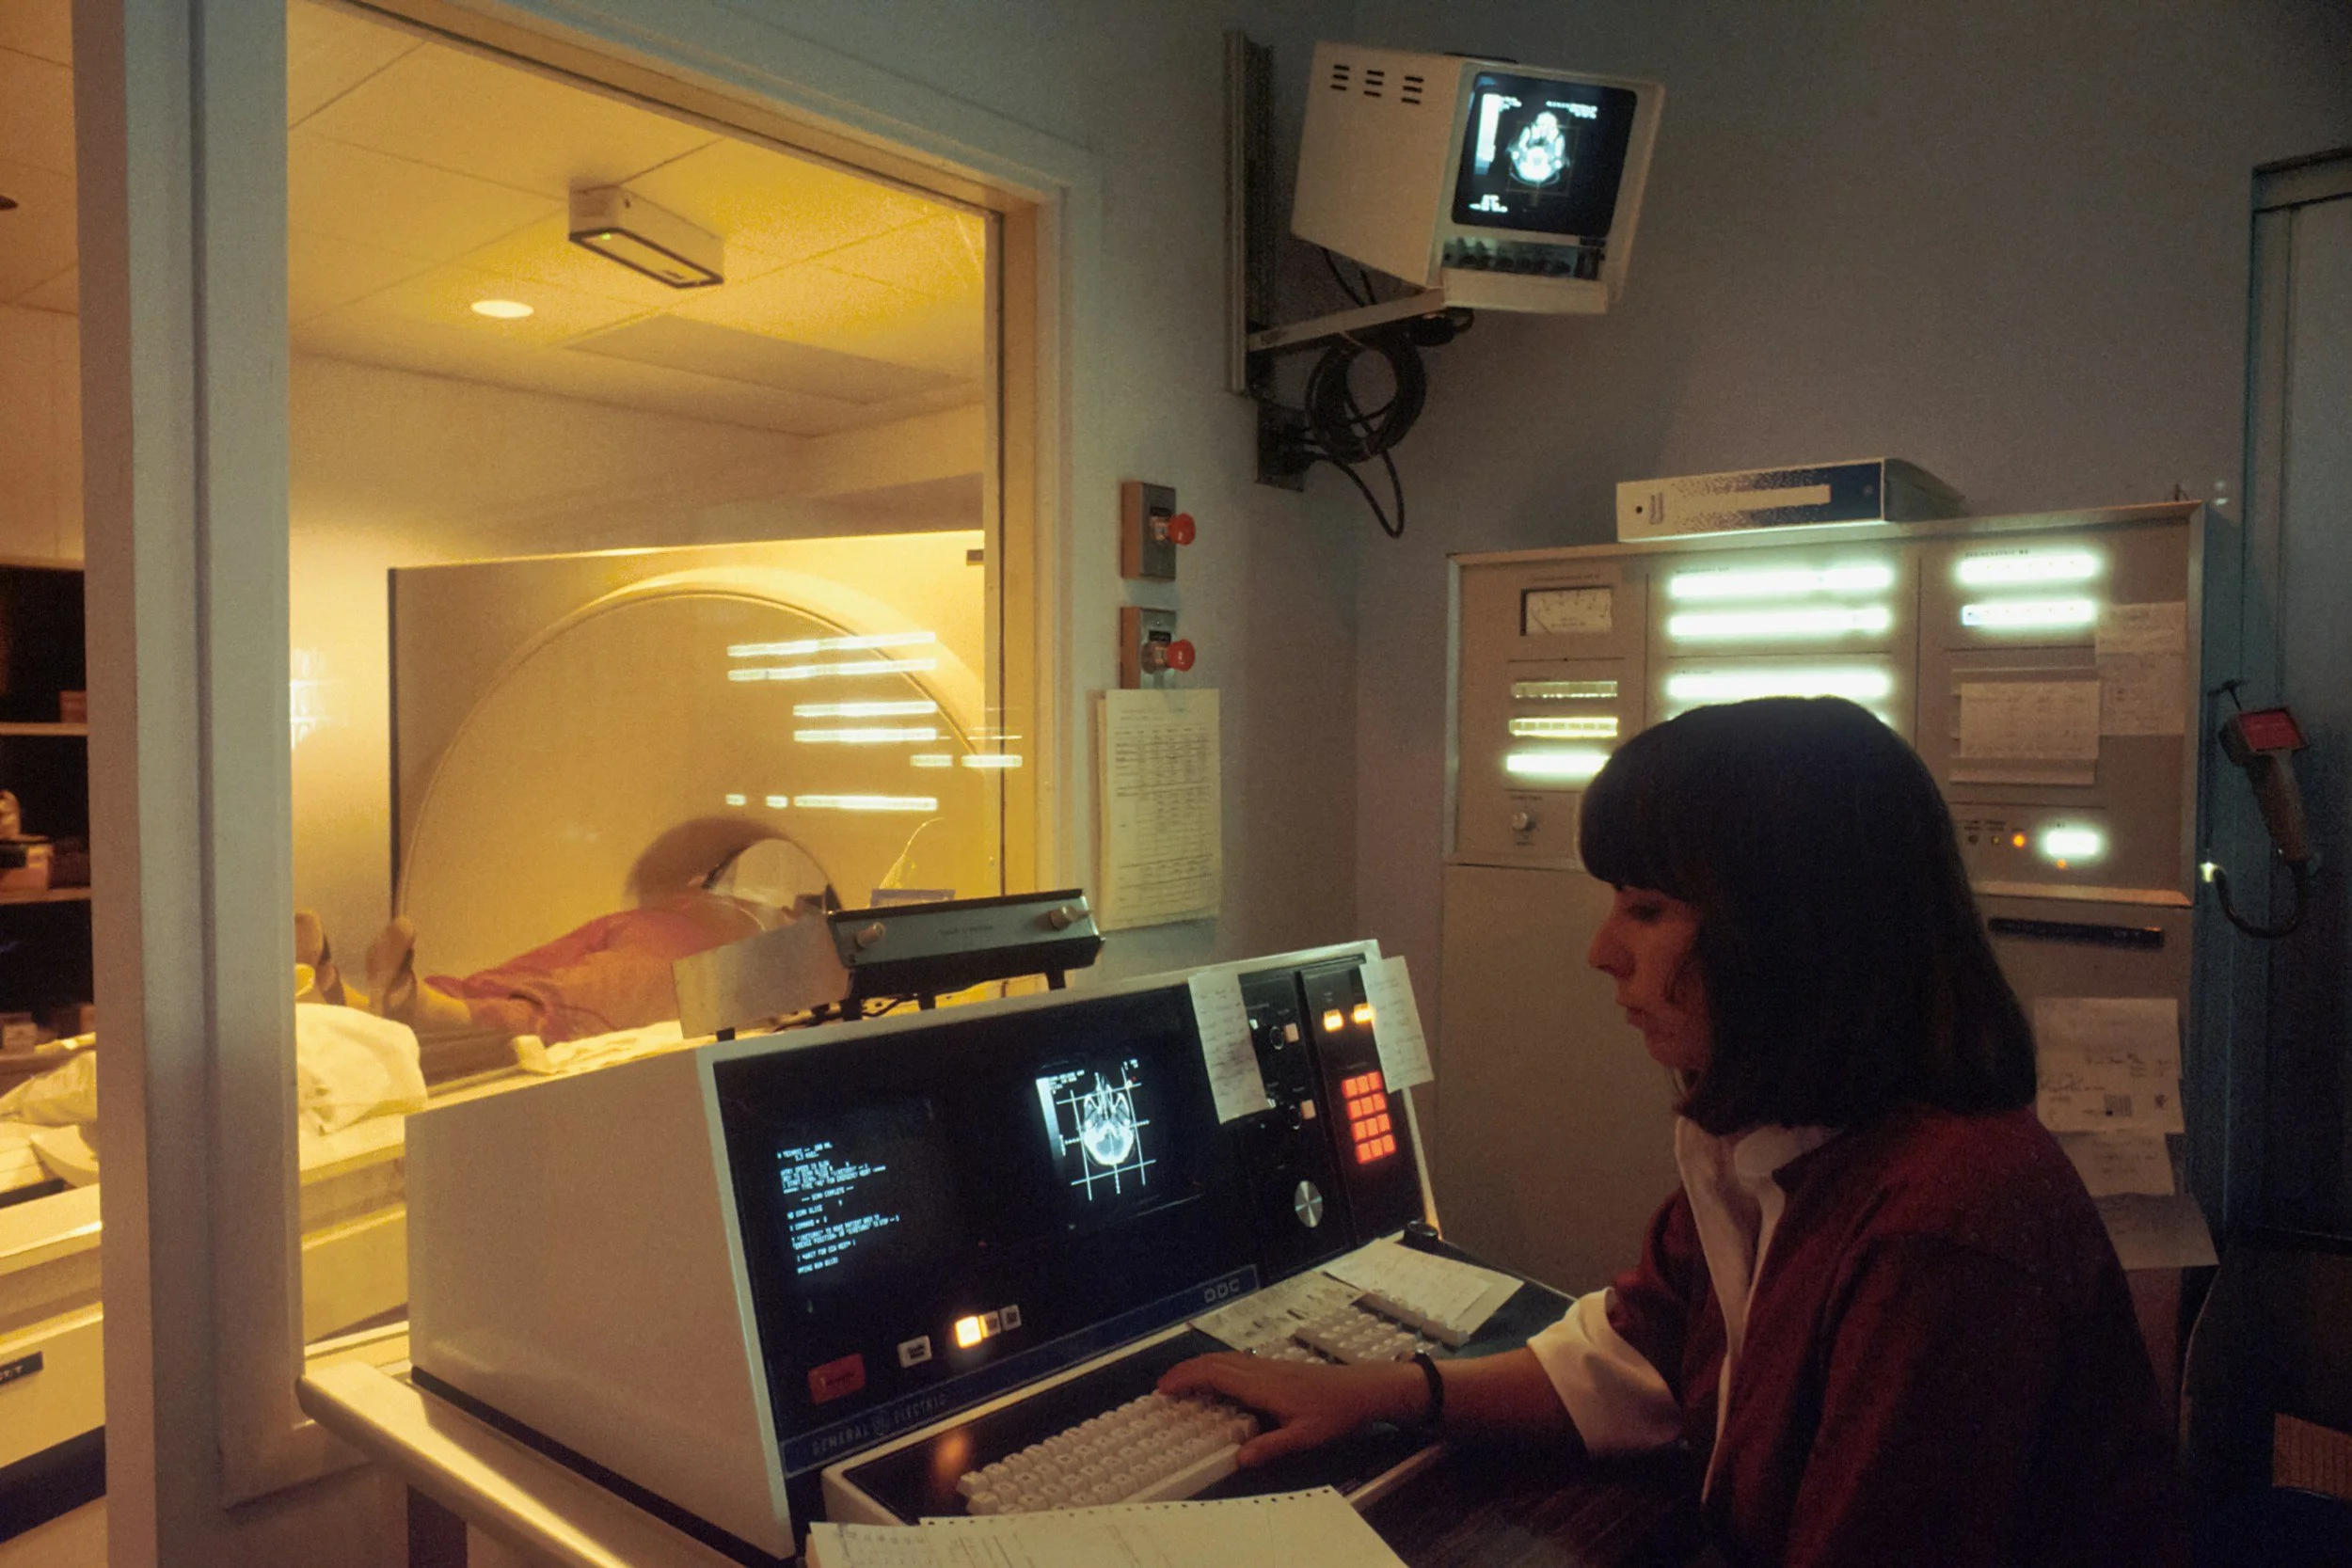

Pour beaucoup de personnes en parcours de soin, l’examen médical n’est pas qu’une simple formalité technique. C’est un moment de vulnérabilité extrême. Entre l’attente dans la salle froide, le bruit imposant de l’IRM et l’appréhension des résultats, une forme d’anxiété de performance médicale s’installe. On a l'impression que notre corps passe un examen dont on redoute la sentence.

Face à la machine, le corps entre souvent en mode "survie". Le cœur s'accélère, la respiration devient haute et courte, et les pensées s'emballent. Cette réponse physiologique amplifie la sensation d'oppression, rendant l'examen encore plus difficile à supporter.

Une fois allongée dans le tunnel de l'IRM ou sur la table du scanner, le bruit peut être envahissant. La clé : Expirez deux fois plus longtemps que vous n'inspirez. Imaginez que vous soufflez dans une paille pour évacuer la pression. Cette expiration longue stimule le nerf vague, responsable de la détente immédiate du rythme cardiaque.